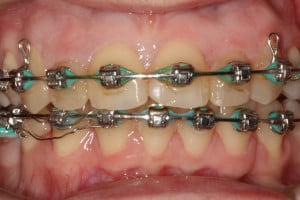

Młoda pacjentka zgłosiła się do naszego gabinetu celem wykonania kompleksowego leczenia zachowawczo-ortodontycznego. Oprócz problemów natury ortodontycznej stwierdzono złą higienę jamy ustnej oraz liczne potrzeby leczenia zachowawczo-endodontycznego. Po wnikliwej analizie telerentgenowskiej oraz analizie modeli zadecydowano o ekstrakcji 2 zębów w łuku dolnym (kła po stronie lewej oraz pierwszego przedtrzonowca po stronie prawej). Plan leczenia obejmował ponadto zamknięcie łuku po brakujących zębach w łuku górnym. Leczenie aktywne trwało 2 lata i 8 miesięcy. W czasie jego trwania pacjentka była regularnie poddawana zabiegom higieny profesjonalnej celem eliminacji zapaleń przyzębia brzeżnego. Po leczeniu aktywnym zastosowano leczenie retencyjne w postaci retainera stałego w żuchwie oraz szyny retencyjnej w łuku górnym.